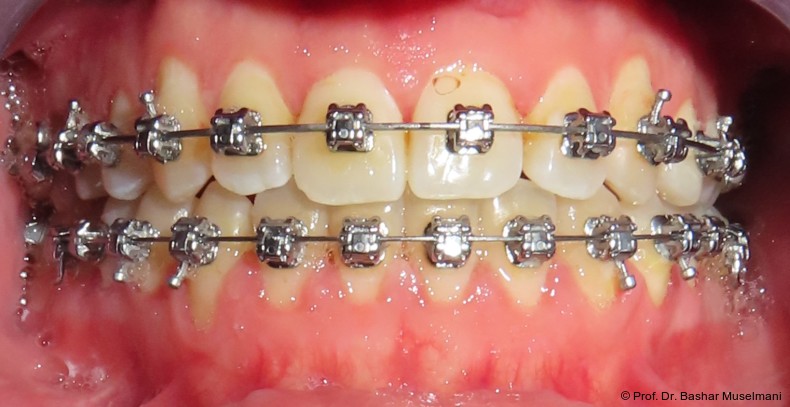

Bogensequenz und mechanische Umsetzung

Der Bogenwechsel erfolgte in einem standardisierten Intervall von acht Wochen. Die Sequenz war in beiden Kiefern weitgehend identisch und wie folgt aufgebaut:

• 0.013" CuNiTi (OK / UK)

• 0.016" CuNiTi (OK / UK)

• 0.018" CuNiTi (OK / UK)

• 0.014 x 0.0275" CuNiTi (OK / UK)

• 0.016 x 0.0275" Edelstahl (OK)

• 0.018 x 0.0275" CuNiTi (OK / UK)

• Abschlussbogen: 0.018 x 0.0275" TMA (OK/UK)

Diese Sequenz ermöglichte eine schrittweise Ausformung der Zahnbögen, eine kontrollierte Torque-Expression sowie eine präzise Feineinstellung in der Abschlussphase (Abb. 5a–e).